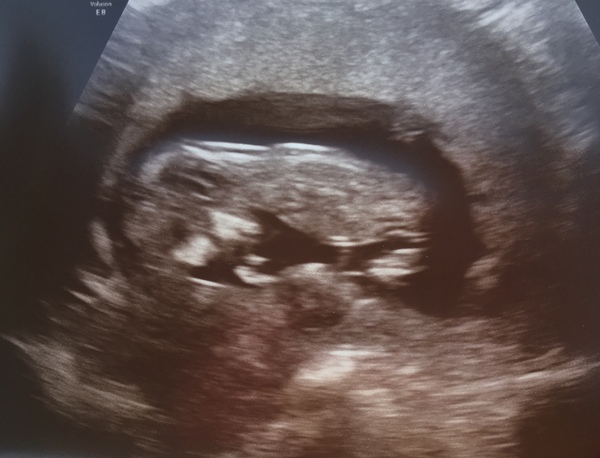

Hi girls. Well I went to the EPU this morning after a bit of bleeding last Thursday and everything is looking ok. Baby is measuring 11+4 perfect for my dates and was wiggling so so much. I cried.

I’ve got my 12 week Scan this Thursday morning and I can’t wait now.

@MagicalCreatures that’s great. Lovely picture.

@MagicalCreatures I'm so sorry you're suffering babe. Hopefully it will sort itself out once baby comes (don't know too much about Fowler's syndrome) BUT... amazing scan!' Eek!! Bet you're excited about Thursday now!!! I'm glad you went today!